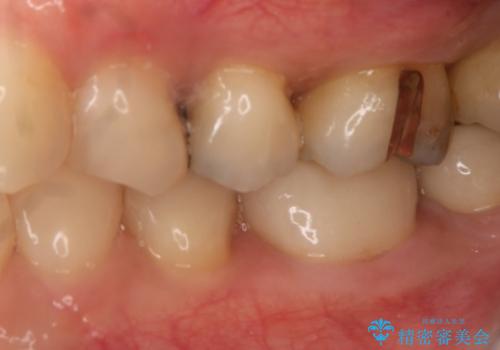

- 左上奥歯の銀歯のやり変えを希望された患者様です。

白くしたいとの事だったので形態・切削量を考慮し、セラミックインレーでの治療を計画しました。